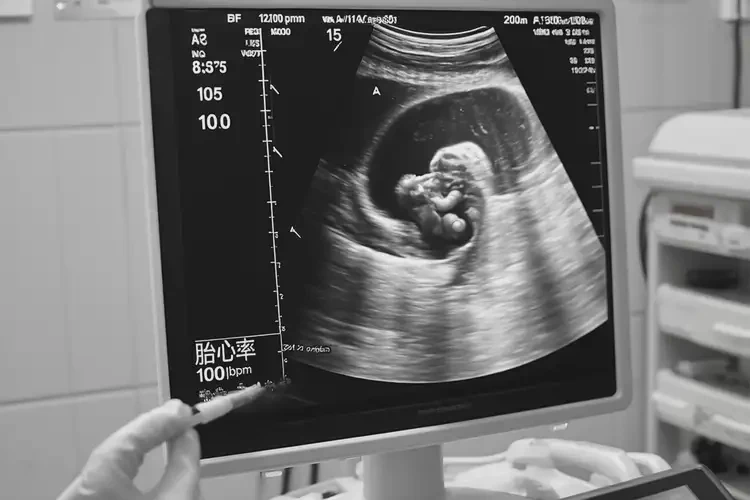

懷孕第15周胎心100左右還能保住嗎

胎心100次/分鐘在懷孕第15周可能提示胎兒存在健康問題,但是否能保住胎兒需綜合多方面因素評(píng)估。

懷孕第15周時(shí),正常胎心率應(yīng)在140-170次/分鐘之間。胎心100次/分鐘明顯低于正常范圍,可能表明胎兒心率過緩,需要引起重視。僅憑胎心率一項(xiàng)指標(biāo)無法確定胎兒是否能保住,還需結(jié)合其他監(jiān)測(cè)數(shù)據(jù)和臨床情況進(jìn)行全面評(píng)估。

懷孕第15周胎心100左右還能保住嗎(圖1)